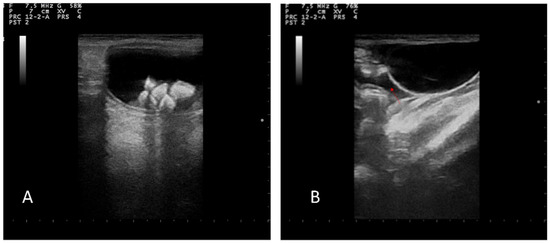

A direct radiographic study of the abdomen with orthogonal projections was performed, using a radiographic system (Morpheus, Gieffe Elettromedicali, Misterbianco (Catania, Italy) and a digital radiography system (Fujifilm Medical Systems, Milan, Italy). This examination showed a loss of soft tissue contrast in the lumbar region, and radiopaque stones in the urinary bladder (Figure 1).

Figure 1.

Lateral radiograph of the abdomen: loss of contrast in the lumbar region (arrows) and a presence of uroliths in urinary bladder.